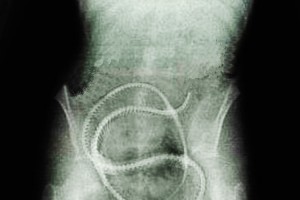

la lombriz solitaria